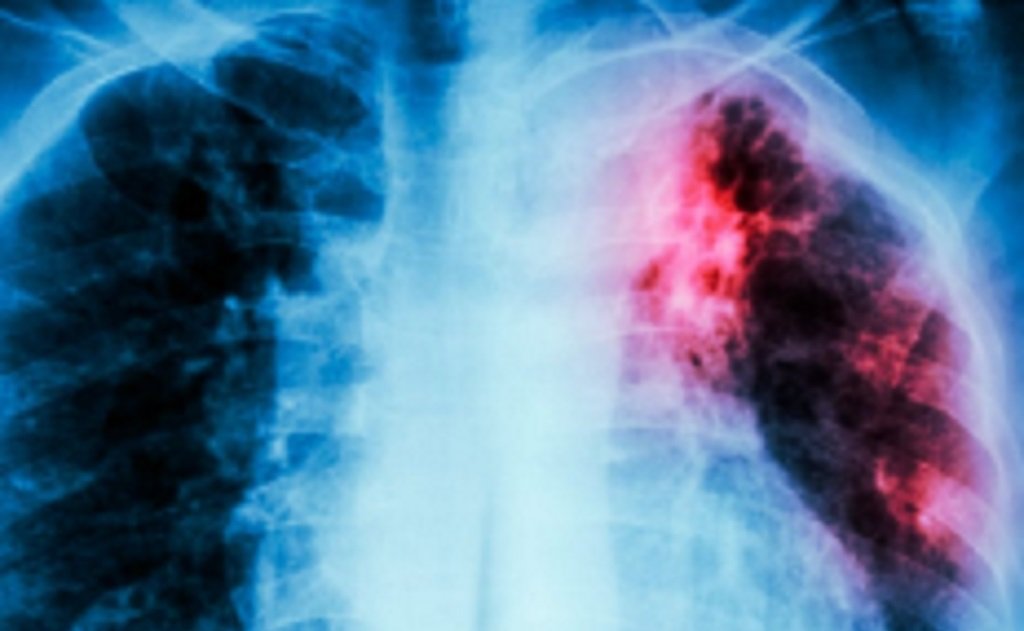

Durante el 2025 se notificaron en la provincia 884 casos de tuberculosis, lo que representa una baja del 8,6% en comparación con 2024, cuando se habían registrado 967 casos. En 2023, el número de notificaciones fue de 945.

Del total de casos confirmados, 43 corresponden a menores de 19 años y 12 presentaron algún tipo de resistencia a los medicamentos. La tuberculosis multirresistente se define como una forma de la enfermedad en la que los fármacos más potentes no resultan eficaces, situación que suele asociarse al abandono del tratamiento o a su incumplimiento según la indicación médica.